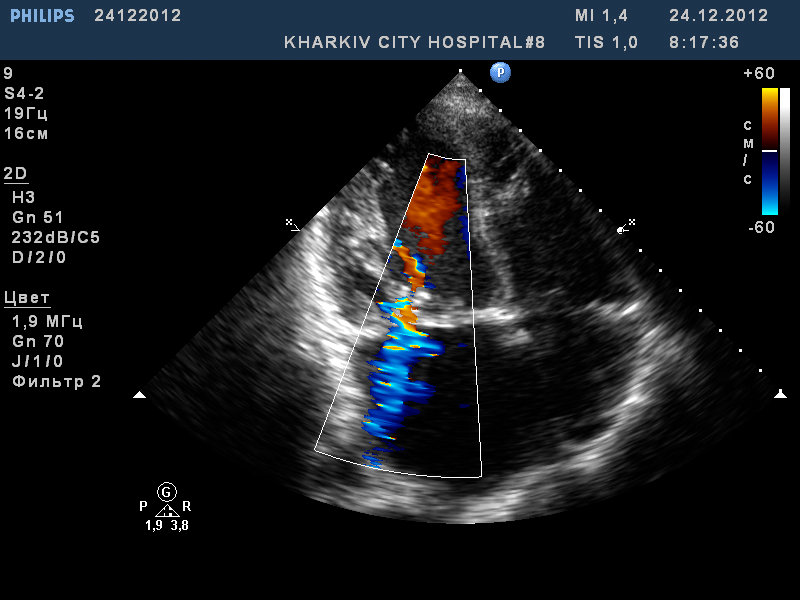

Митральный стеноз, частичный отрыв хорд передней створки МК

Пациент 52 лет. Поступил с нарушение ритма.

Заключение узи : склеротические изменения аорты, фиброзные изменения створок аортального клапана, незначительная недостаточность аортального клапана, частичный отрыв хорд передней створки митрального клапана, значительный митральный стеноз, умеренная МН, дилатация левого предсердия (6,0см), гипертрофия левого желудочка.